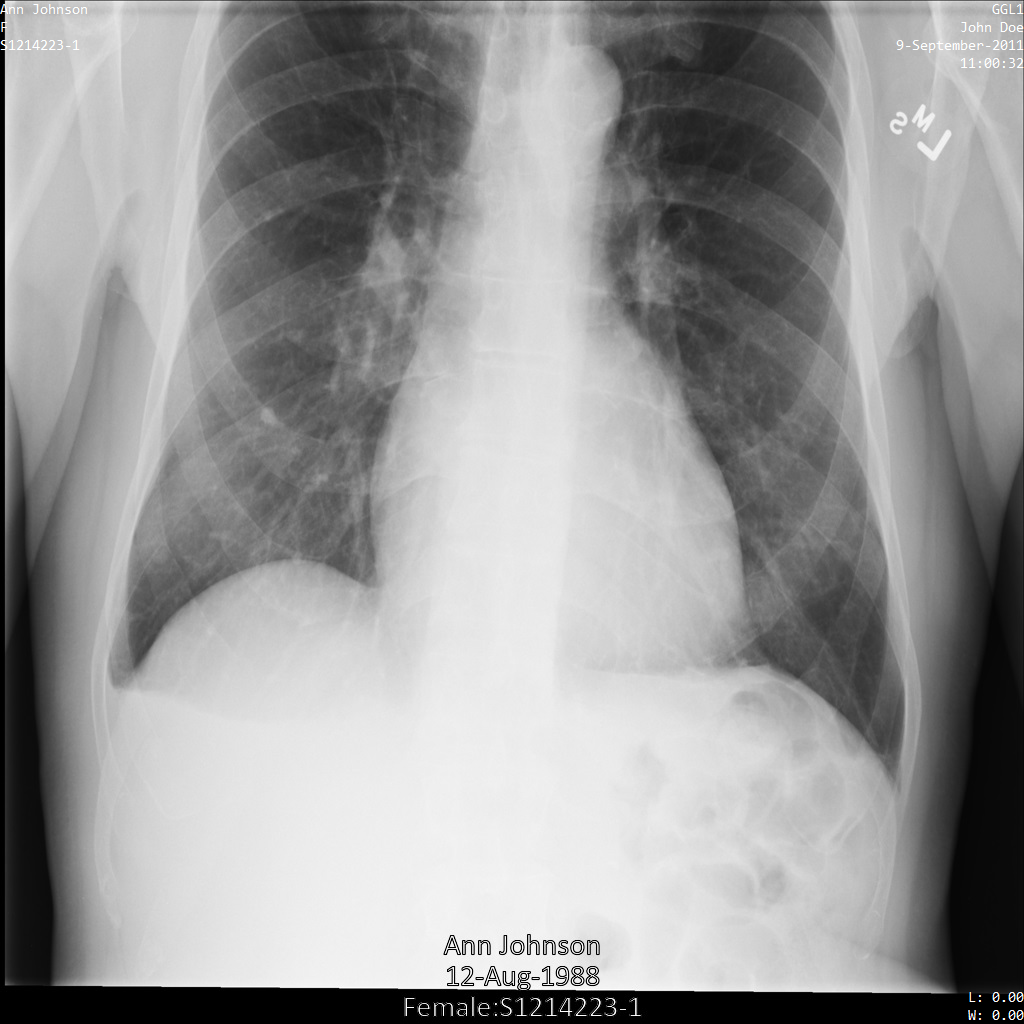

Después de enviar la imagen a la API de Cloud Healthcare, la imagen aparece de la siguiente manera. De las etiquetas proporcionadas en la removelist, solo se quita PatientBirthDate en la imagen, ya que es la única etiqueta de la lista de eliminación que corresponde a los metadatos visibles en la imagen.

Si bien PatientBirthDate en la esquina superior de la imagen se ocultó de acuerdo con la configuración de la removelist, la PHI de efecto quemado que se encuentra en la parte inferior de la imagen permanece. Para quitar también el texto quemado, consulta Cómo ocultar el texto quemado de las imágenes.